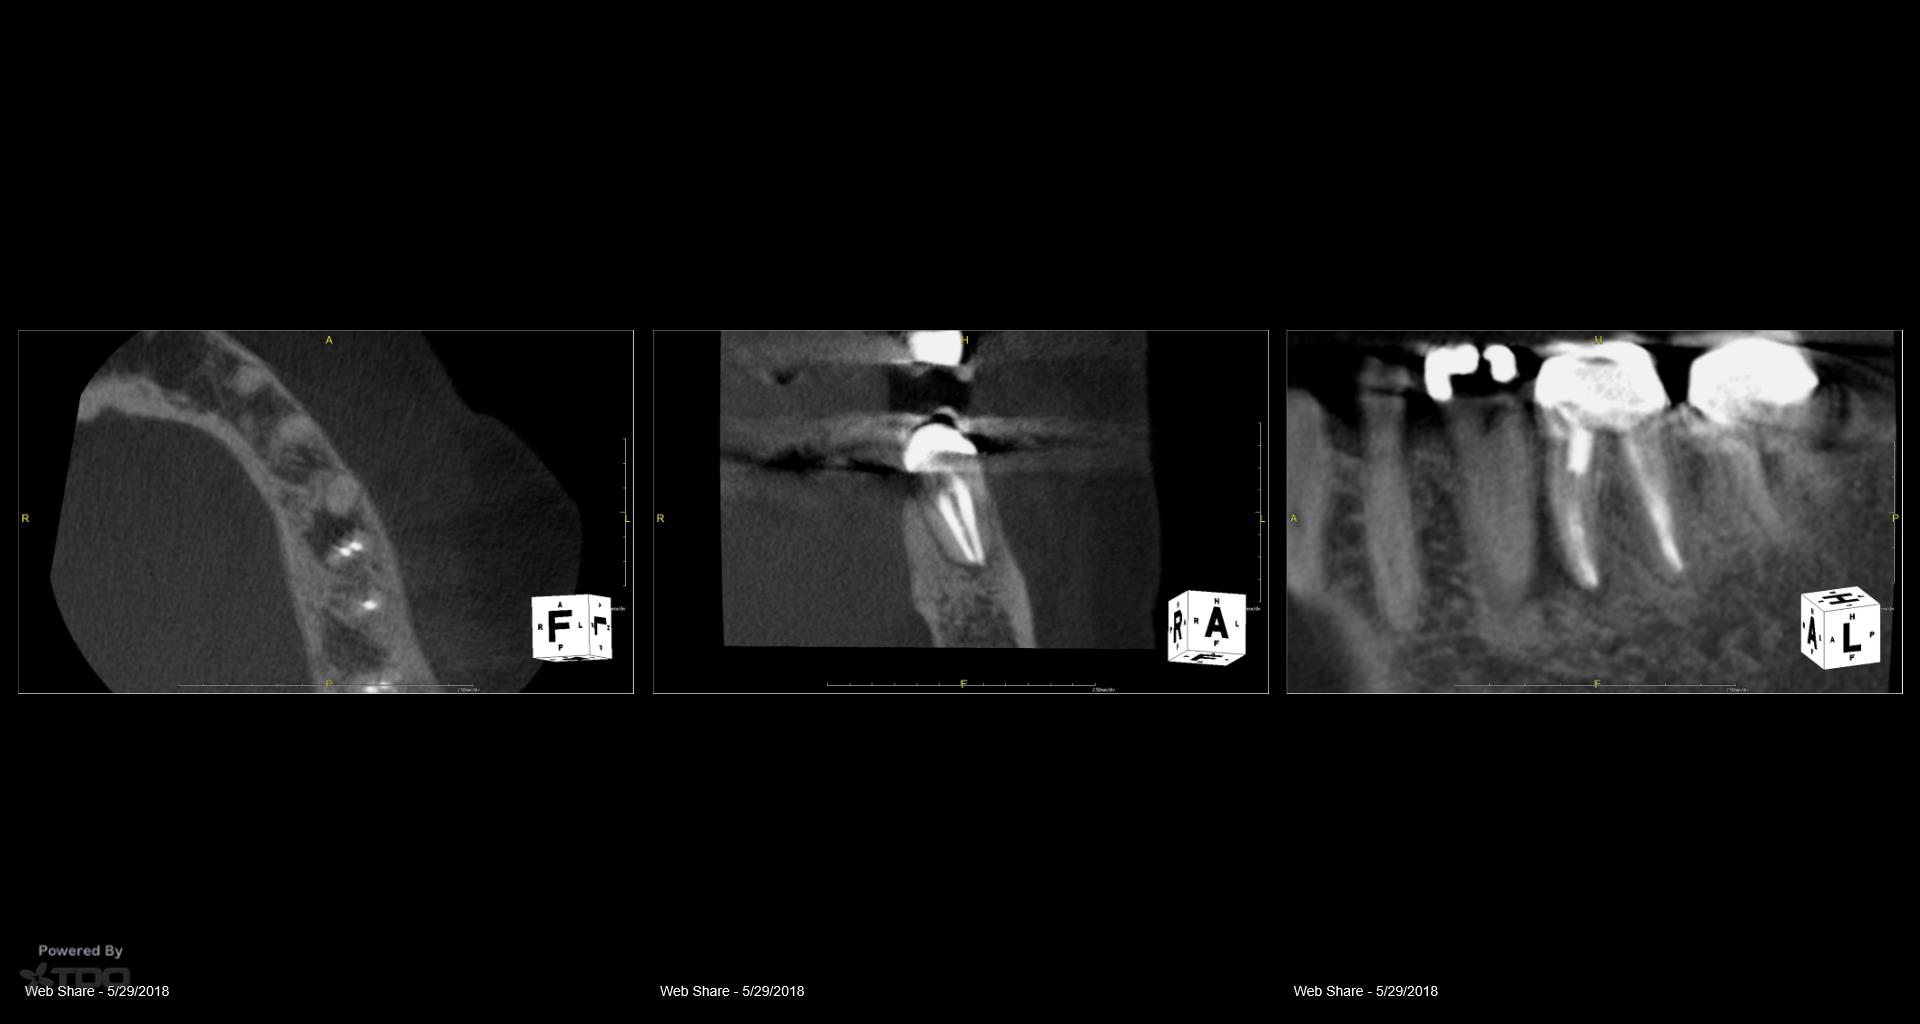

Patient in for a sinus tract check recall today asking questions…… All treatment done by endodontists. Always done in a single visit. The 2nd endodontist told the patient she was “cured”. He never checked her again. When she called and said she may have a problem… they told her it wasn’t necessary. Her GP told her to have it extracted. Is it fractured? Is it a failing RCT that can be saved? How does one tell? To me, to do a retreatment like this in a single visit….. Well…it isn’t the way I would like to be treated. Because you end up with cases like this. By the way: no symptoms. gbc